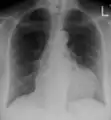

| An ECG showing pericarditis, with ST elevation in multiple leads and slight reciprocal ST depression in aVR. | |